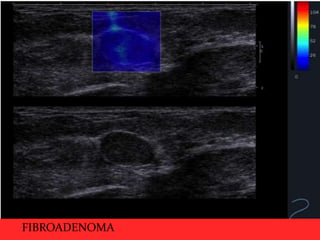

Benign lesions demonstrating : homogenoeus oval shape and very soft

elastogram, which also appears the same size on both gray-scale and shearwave elastography.. Clustered microcysts

FIBROADENOMA